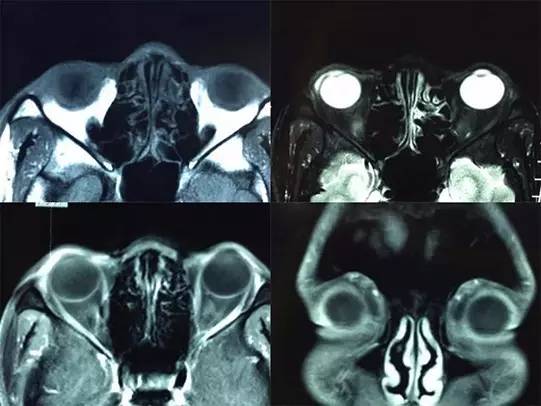

患者男性,39岁,因右眼结膜肿物7年就诊。患者自述7年前开始发现右眼球结膜新生肿物,肿物质软无压痛,曾就诊于当地医院,给予眼药水滴用,具体诊疗不详。近来发现右眼球结膜肿物逐渐变大,故就诊于首都医科大学附属北京同仁医院眼肿瘤专科。患者自发病以来无眼痛、畏光、分泌物增多等症状;近期无感冒发热史,无外伤及手术史;个人史和家族史无特殊。患者一般情况检查良好,生命体征平稳,神志清,心、肺、腹部检查未见异常。眼科检查:双眼视力1.0,双眼眼压 15mmHg,右眼颞下方球结膜肿物,局限性隆起,肿物质地较柔软(图1),双眼角膜清,KP(-),前房中深,Tyn(-),瞳孔圆,对光反射正常,晶状体清,视乳头边界清晰,色泽正常,黄斑中心凹反光可见。MRI扫描右眼前节可见肿物影,T1WI呈等信号,T2WI呈略高信号,增强扫描肿物可被强化(图2)。门诊以结膜肿物收入院,入院后经过积极术前准备,在全身麻醉下行结膜肿物切除术,术中见结膜下肿物边界不清,肿物似含黏液胶状物质。手术后病理组织学检查结果显示结膜黏液囊肿。患者术后5天出院,随诊至今未见复发。

图2. 患者术前眼部MRI影像

影像学检查对发现和评估黏液囊肿有重大意义。CT扫描因囊肿内黏液含有蛋白质浓度存在差异,故CT影像学可表现为低密度、等密度或高密度[10]。大多数黏液囊肿CT扫描呈低密度或者等密度信号,一般和脑或者颞肌的密度相同[11]。当囊肿伴有炎症时,囊肿不增强,但囊肿与囊壁之间可呈环状增强[12]。B超扫描可发现病变,可显示病变的暗区和液性平段[13],但细节不如MRI清晰[14]。MRI扫描的组织分辨率高[15],可以明确周围组织和病变的关系。信号密度与囊肿内蛋白质和水的含量有很大关系,如果水分含量高,则T2呈高信号。如果蛋白质含量高,则T1呈高信号。当蛋白质浓度特别高时,T1WI和T2WI均呈低信号[16,17,18]。